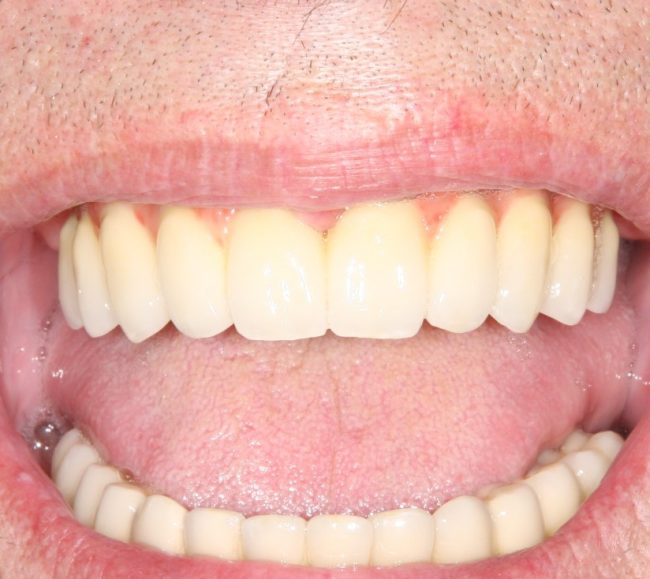

Рекомендации по установке имплантов. Для всех. Часть III